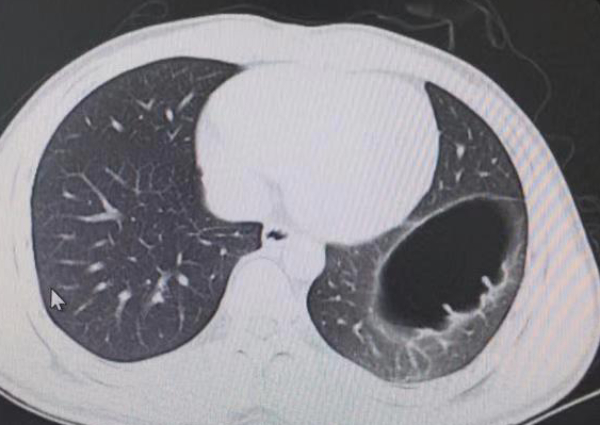

Ảnh chụp cắt lớp vi tính cho thấy thoát vị cơ hoành của Mai.

Trước sự ngạc nhiên của anh, bác sĩ nhanh chóng chẩn đoán và phát hiện ra anh bị thoát vị cơ hoành bẩm sinh. Điều này xảy ra khi cơ hoành ngăn cách ngực với bụng, có một lỗ mở cho phép các cơ quan bụng di chuyển lên trên ngực.

Trong trường hợp của Mai thì anh bị bẩm sinh, khiếm khuyết này đã có từ lúc sinh ra.

Bác sĩ Feng Jinhang đã quan sát và nghe thấy âm thanh kỳ lạ trong ruột của anh, điều này đúng như phỏng đoán ruột đã di chuyển lên ngực. Anh cần phải thực hiện một cuộc phẫu thuật để di chuyển các cơ quan nội tạng về đúng vị trí và sửa chữa lại cơ hoành.